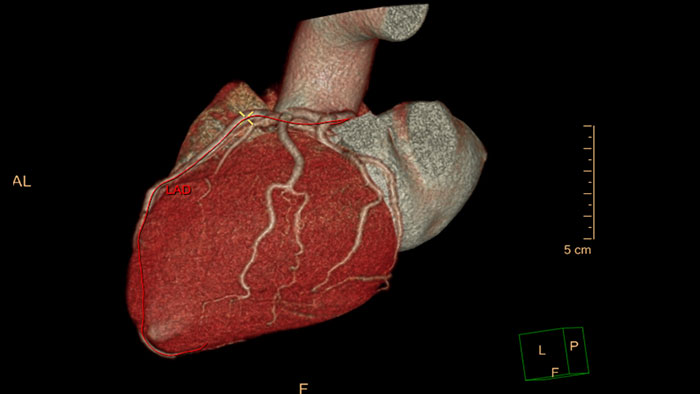

CT imaging in TAVI to advance patient care

Provides 2D and 3D visualization and automated measurements designed to assist in proper TAVI-device sizing, on contrast-enhanced, prospectively ECG-gated axial or retrospectively gated helical CT images.

Streamlined modeling workflow

Allows to view volumetric images of anatomical structures, perform segmentation, edit and combine segmented elements (tissues) into a 3D model.